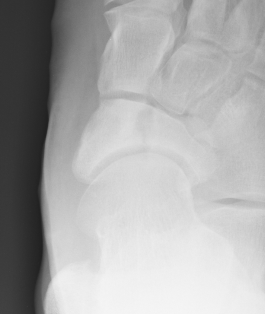

Imaging

Acute, minimally displaced navicular fracture

Acute displaced navicular fracture